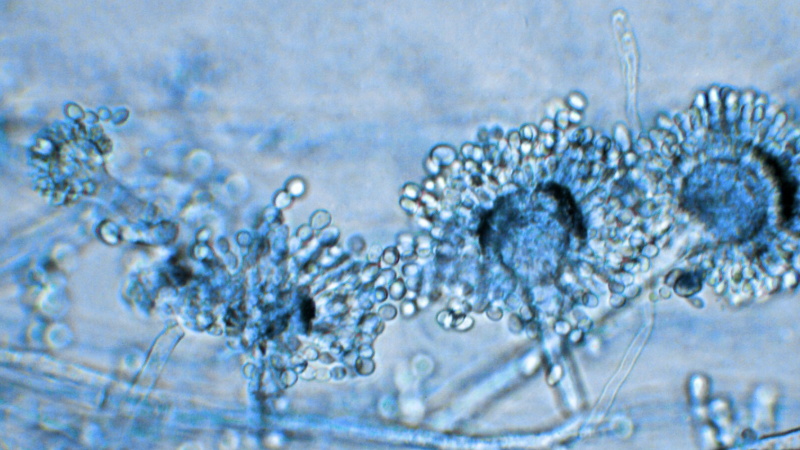

Test rápido para diagnóstico de aspergilosis

La aspergilosis es una infección causada por hongos ...